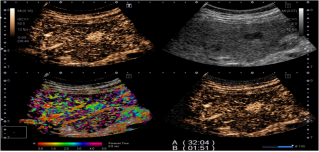

2. 全面的造影功能(Contrast Enhancement Ultrasound):系统可以四幅图(二维, 造影, 微血管累积模式MFI/到达时间参数成像P-MFI, 混合模式)同时显示,方便进行介入治疗方案的选择和即刻疗效的评估。

全面的造影模式包括以下几种模式:

精确造影成像技术(PCI)- 独有的技术

极大提高了造影成像的敏感度与图像的细微分辨率。

差量谐波造影成像技术(DCI)- 独有的技术

优异的穿透力和对比分辨力,最佳的造影成像的远场显示及灌注细节。

血管识别成像(VRI)- 独有的技术

1. 方向性地观察肿瘤血管的走向,利于肿瘤新生血管的判断和分析及发现微小病灶。

2. 二维组织成像与造影剂灌注情况的同时显示。

3. 将造影剂的灌注状态以三种不同颜色同时显示,用红/蓝色方向性地显示较大血管的灌注,以绿色高分辨地显示微细血管的灌注,使得造影剂达到最佳的显示效果。

到达时间参数成像(P-MFI):

1. 对于具有不同血供特点的疾病方便的实施鉴别诊断。

2.对造影剂的灌注按时间顺序彩色编码,清晰显示微血管造影剂灌注。